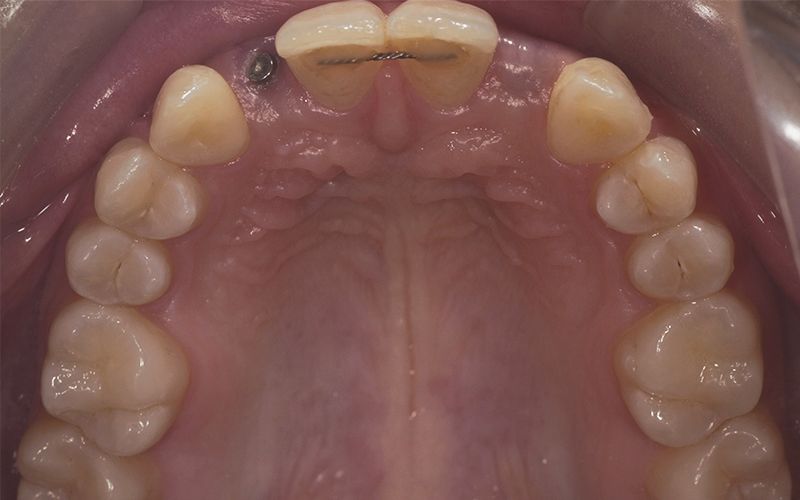

Al cabo de todo este tiempo se realizó un CBCT maxilar para iniciar la planificación de la cirugía de colocación de dos implantes en posición de 12 y 22. Durante el análisis de las imágenes radiográficas, tal y como indican las mediciones que se realizaron, se observó una limitación de espacio en sentido mesio-distal entre 11 – 13 y 21 – 23, que iba a impedir la colocación de dos implantes estándar de 3.3 mm de diámetro.

Dadas las circunstancias y para buscar una resolución óptima del caso, se decidió utilizar implantes Biomimetic Pearl de diámetro reducido de 2.8 mm de Avinent Implant System. Estos mini-implantes disponen de una línea protésica para rehabilitaciones unitarias y, dentro de su amplia gama, encontramos el que se ajustaba mejor a las exigencias del caso, permitiendo mantener perfectamente la distribución de espacio para poder respetar la biología de la rehabilitación.